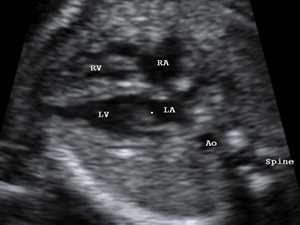

The 4-chamber view of fetal heart